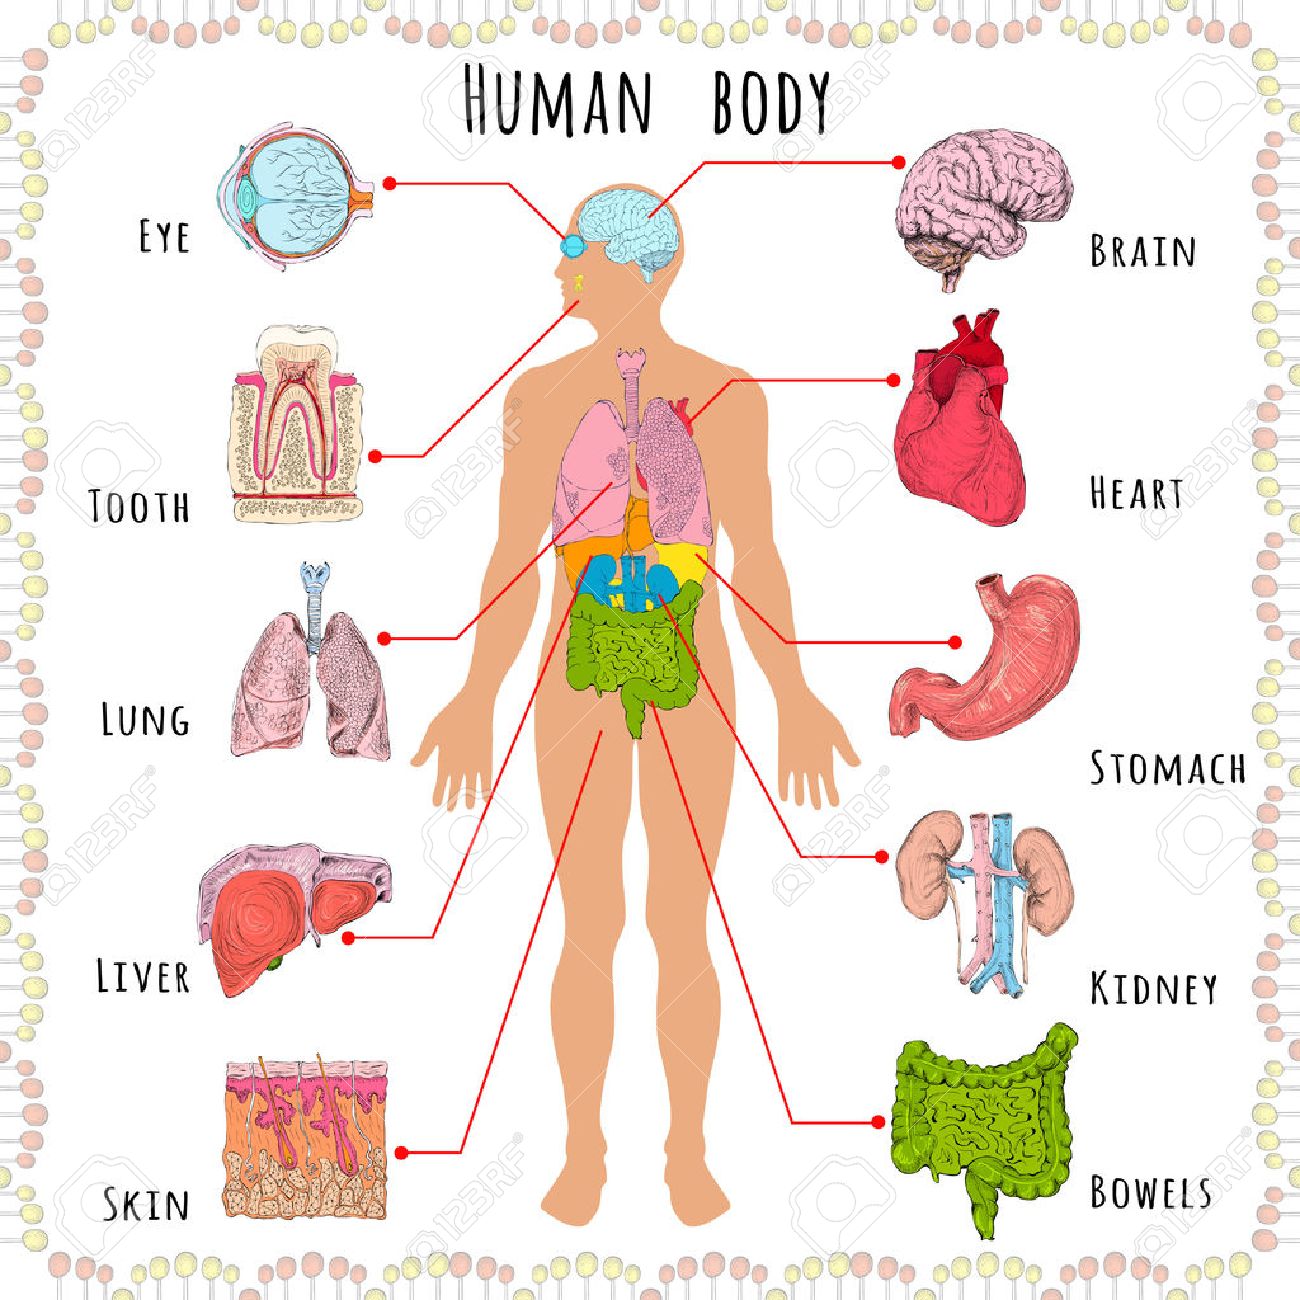

Human Male Organ Locations Person persons eg she s an interesting person people there are so many people travelling here people peoples

Human Male Organ Locations

Human Male Organ Locations

Male Organ Chart Stock Photography CartoonDealer 55486388

More picture related to Human Male Organ Locations

Humbody Organs Drawing At GetDrawings Free Download

The Human Organs Diagram

Male Body Parts Diagram

Body Diagram Of Organs

Body Diagram Of Organs

Human Body Organs Diagram Male

Human Male Organ Locations - [desc-13]